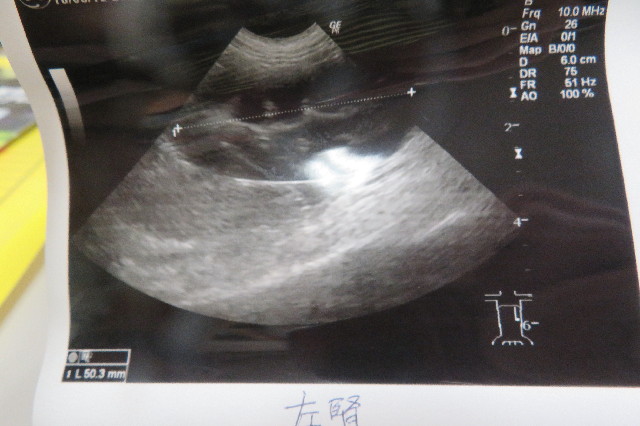

【膀胱を横から見たところ】

膀胱の壁が晴れています。

●石はありません

腎臓に石があることもあるそうですが、“もにちゃん”の腎臓に異常はありませんでした。